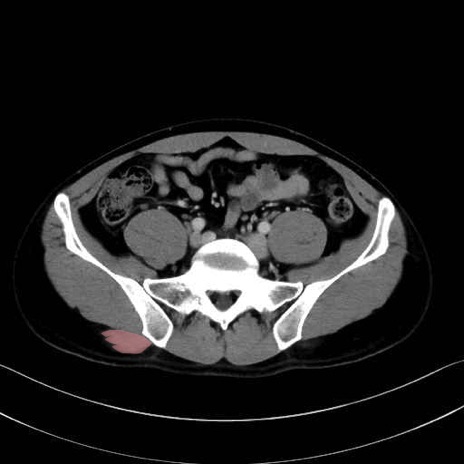

梨状筋 (Piriformis)